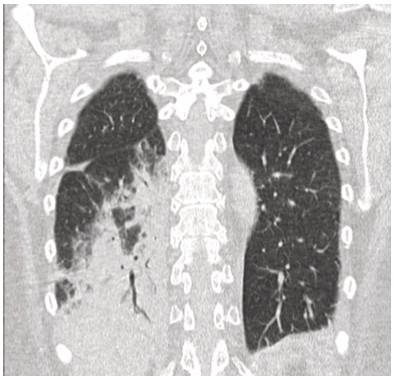

Mujer de 73 años procedente de Australia con antecedentes de hipertensión arterial, depresión, tiroiditis de Hashimoto e hipotiroidismo secundario. En las últimas semanas, como parte de su recorrido por Sudamérica, visitó Chile, Brasil, Argentina y Perú. En este último y durante su estancia en Machu Picchu, debuta con un cuadro clínico caracterizado por astenia, disnea de moderados esfuerzos, tos seca y cefalea opresiva holocraneana, tratada con medicación no especificada con mejoría parcial. Sin embargo, pocos días después y tras su llegada a Ecuador los síntomas se agudizan con aumento de la frecuencia e intensidad de la tos, así como la disnea y el compromiso general caracterizado por astenia, alza térmica y escalofrio. Tras esta presentación clínica es ingresada en el servicio de Emergencia destacando en la valoración clínica taquipnea (24 respiraciones por minuto), hipoxemia medida por pulsioximetría en 79%, con necesidad de aporte de oxígeno suplementario, taquicardia (100 latidos por minuto). En la auscultación pulmonar con presencia de crepitantes difusos y sibilancias basales, además edema de miembros inferiores. Dentro de la evaluación complementaria destaca la presencia de leucocitosis y neutrofilia, elevación de proteína C reactiva y la elevación significativa del dímero D (tabla 1). El panel respiratorio por PCR de 13 patógenos fue negativo. En los estudios de imagen infiltrados alveolares multilobares con broncograma aéreo y un estudio angiotomografico sin evidencia de defectos de llenado que sugieran tromboembolia pulmonar (TEP) (figuras 1-3).

Figura 1. Tomografía de tórax simple de alta resolución, corte coronal: presencia de consolidado en lóbulo superior izquierdo y región apical del segmento 6, signo del halo inverso.

Figura 2. Tomografía de tórax simple de alta resolución, corte coronal: presencia de consolidado con broncograma aéreo en lóbulo inferior derecho.

Figura 3. Tomografía de tórax de alta resolución, corte axial. Izquierda: presencia de consolidado en lóbulo inferior derecho. Derecha: Língula.